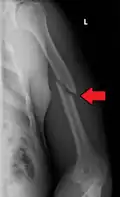

Midshaft humerus fracture with callus formation

Middle

Middle fractures are usually caused by either physical trauma or falls. Physical trauma to the humerus shaft tends to produce transverse fractures whereas falls tend to produce spiral fractures. Metastatic breast cancer may also cause fractures in the humerus shaft.[12] Long spiral fractures of the shaft that are present in children may indicate physical abuse.[5]

Definitive diagnosis of humerus fractures is typically made through radiographic imaging. For proximal fractures, X-rays can be taken from a scapular anteroposterior (AP) view, which takes an image of the front of the shoulder region from an angle, a scapular Y view, which takes an image of the back of the shoulder region from an angle, and an axillar lateral view, which has the patient lie on his or her back, lift the bottom half of the arm up to the side, and have an image taken of the axilla region underneath the shoulder.[9] Fractures of the humerus shaft are usually correctly identified with radiographic images taken from the AP and lateral viewpoints.[12] Damage to the radial nerve from a shaft fracture can be identified by an inability to bend the hand backwards or by decreased sensation in the back of the hand.[5] Images of the distal region are often of poor quality due to the patient being unable to extend the elbow because of pain. If a severe distal fracture is suspected, then a computed tomography (CT) scan can provide greater detail of the fracture. Nondisplaced distal fractures may not be directly visible; they may only be visible due to fat being displaced because of internal bleeding in the elbow.[7]

Fractures of the humerus shaft are most often uncomplicated, closed fractures that require nothing more than pain medicine and wearing a cast or sling. For midshaft fractures up to 12 weeks may be required for healing.[17]